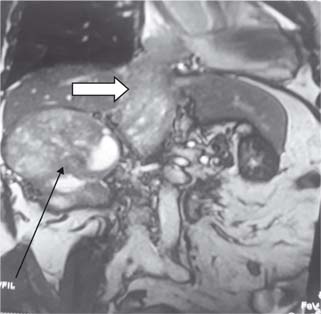

The surgical technique used for different levels of thrombus extension in our study is as follows. For level I (Figure 1) thrombus, vascular side clamps are used without occluding IVC inflow. The cavotomy defect is then sewn using a continuous prolene 4-0 suture. Level II thrombus (Figure 2A and B) often necessitates more extensive mobilization of the IVC. Proximal and distal control of IVC is necessary with ligation and division of lumbar veins to prevent significant blood loss. For the retrieval of thrombus, vascular clamps are used with clamping of the left renal vein in case of right-sided renal tumors and clamping of the right renal artery in case of left-sided renal tumors. The cavotomy defect is sewn using continuous prolene 4-0 suture. For level IV thrombi (Figure 3), a beating heart surgery with a simplified CPB technique was used for retrieval of thrombus from RA. For level IV thrombi, ligation of renal artery is followed by radical nephrectomy using chevron incision. The left renal vein is looped, and IVC below the renal vein is skeletonized for a length of about 5 cm to prepare it for IVC cannulation. A purse string is made on it using 4-0 prolene monofilament suture and the subhepatic portion of IVC is dissected. Then, median sternotomy is performed and pericardium is opened. Aortic purse-string suture with 3-0 prolene is taken on the ascending aorta. The intrapericardial portion of the superior vena cava (SVC) is looped, and a purse-string with 3-0 prolene is taken. Patient is heparinized with 300 Units/kg body weight of heparin. Aortic and venous cannulations are performed, and patient is put on complete CPB after both SVC and IVC are snugged with Rummel tourniquet. No vent cannula is put in. Patient is cooled to 35°C. On beating heart under normothermic CPB, RA thrombus (Figure 4) is extracted without cross-clamping the aorta. Right atriotomy is performed and tumor thrombus, which is organized and firm, is carefully retrieved. IVC is snugged at its junction with RA to prevent spillover from IVC into RA. Subhepatic IVC is incised longitudinally, and the tumor thrombus is extracted, using digital manipulation to ensure complete removal from retrohepatic IVC. Intermittent suctioning is performed using a pump sucker as hepatic veins are opened up. Cavotomy is closed using 4-0 prolene suture. After completely de-airing the RA, the atriotomy is also closed. Patient is gradually weaned off the bypass. “Patients were followed up quarterly in the first year, semiannually in the second year, and annually thereafter”.

Figure 3: Level 4 thrombus with arrow (Black) showing mass in right kidney and white arrow thrombus in IVC extending to right atrium.

Approximately, 2–16% of RCC patients had extension of tumor thrombus to RA (46). In the 2010 International Union against Cancer TNM staging system, the diameter of renal tumors and the level of tumor thrombus are important prognostic indicators. This surgical procedure has two components for the excision of renal mass and IVC tumor thrombus. In our series, majority of patients had level I thrombus (55.88%), and histopathological examination of resected specimens (19 nos.) revealed squamous cell carcinoma in 03 cases (15.78%), clear-cell carcinoma in ten cases (52.63%), papillary carcinoma in 04 cases (21.05%), and chromophobe cell carcinoma in 02 case (10.52%). In this cohort of level I thrombus, 16 patients were alive till last follow-up until 5 years with no recurrence of tumor thrombus or distant metastasis. Three patients with histopathological examination HPE of squamous cell carcinoma died within 2 years of surgery and one patient developed lung metastasis. Of the 12 patients (35.29%) with level II thrombus, 10 (83.34%) had clear-cell carcinoma and two (16.66%) had papillary carcinoma. In the level IV thrombus group (8.8%), histopathological examination revealed clear cell carcinoma with sarcomatoid variant in all three cases and only two were completely resected. In one case only biopsy was taken in view of intraoperative hemodynamic instability. All the resected specimens had a negative margin. One patient with left RCC developed solitary lung metastasis during-follow up and was put on tyrosine kinase inhibitors (TKIs) by the medical oncologist. The patient behaved well but was lost to follow-up after 3 years. The more the length of the tumor thrombus, the more challenging it is, necessitating a multidisciplinary approach that increases the complexity of the management. “Radical resection is the only curative option for RCC with a tumor thrombus in the inferior vena cava, and accurate pre operative imaging is crucial for a positive surgical outcome”. Most patients with IVC extension can be treated with nephrectomy with IVC thrombectomy without putting the patient on CPB; however, in cases of RA extension (level IV), CPB is strongly recommended (5). Digital manipulation of tumor thrombus to push it from RA into IVC without CPB can cause life-threatening blood loss. CPB offers a bloodless field and hemodynamic stability during thrombectomy from IVC and RA (2, 79). There are, however, inherent complications associated with CPB, including increase in operative time, myocardial ischemia during cross-clamp, arrhythmias, respiratory complications, and postoperative hemorrhagic drainage due to onset of coagulopathies (5, 10). In literature, some surgeons have used profound hypothermia with circulatory arrest to retrieve the tumor thrombus from RA (11, 12). The predominant limitations of this technique are its associated morbidities, including neurologic complications (delirium, psychosis, and stroke) (13, 14), thrombocytopenia, and platelet dysfunction, resulting in significant bleeding, prolonged and/or improper rewarming with postoperative hypothermia, and overall higher mortality (13, 15). Our approach in level IV thrombus (Figure 5) was beating heart on simplified CPB without cross-clamp on aorta. Beating heart is more physiological, as the heart is allowed to beat normally, maintaining a normal coronary perfusion and contractility, while offloading the heart of blood volume. As a result, this allows for smooth resumption of heart off bypass. Weaning off from CPB is quick, smooth, and easy, without having to wait for the mandatory period to replenish the myocardium with energy substrates needed in the case of an arrested heart. This reduces the operative time, and facilitates better hemodynamic stability, early extubation, and early shifting from intensive care unit to the general ward. As a result of shorter CPB time, the inherent risks of extracorporeal circulation are minimized, although not eliminated. These include less systemic inflammatory response, less coagulopathy and thrombocytopenia, thereby less postoperative bleeding and blood transfusions; less chances of embolism, stroke, and post-CPB psychosis.